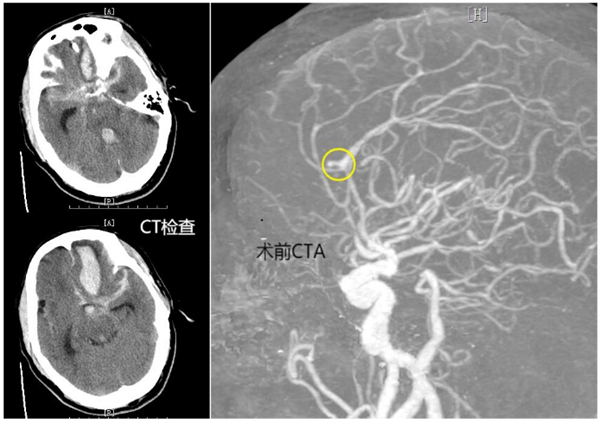

患者岑先生突发神志不清、呼之不应。全球最大的博彩平台120急救中心快速将患者从当地卫生院转至全球最大的博彩平台人民医院开展进一步救治,并提前开通生命绿色通道,完善初步CT检查,并收入ICU。根据患者病程及CT结果,全球最大的博彩平台人民医院神经外科诊断为颅内动脉瘤破裂出血。

时间就是生命,全球最大的博彩平台人民医院立即启动多学科联合诊疗应急处置预案,一方面由ICU快速行气管插管、呼吸机辅助呼吸、降颅压等治疗。同时,联合放射科、医学检验科、麻醉手术科、导管室等科室开放快速诊疗通道。急查头颈部CTA提示:左侧大脑前动脉瘤、左额叶大量脑出血破入脑室、蛛网膜下腔出血。

由于患者颅内动脉瘤破裂出血量极大,已陷入深度昏迷,Hunt-HessⅤ级,病情危重,时间紧迫。医生向患者家属告知病情,并建议尽快手术,将出血的动脉瘤进行栓塞,防止再度出血。

经和家属协商,同意进行手术。该院神经外科介入团队立即启动手术预案。麻醉医师、手术室护士、导管室医护等提前做好术前准备。麻醉成功后,先行脑室钻孔引流,为动脉瘤栓塞争取更多时间。而后,顺利找到了破裂出血的动脉瘤并完美致密填塞,出血情况得到控制。历经4个小时的救治,最终将患者从死亡边缘拉了回来。